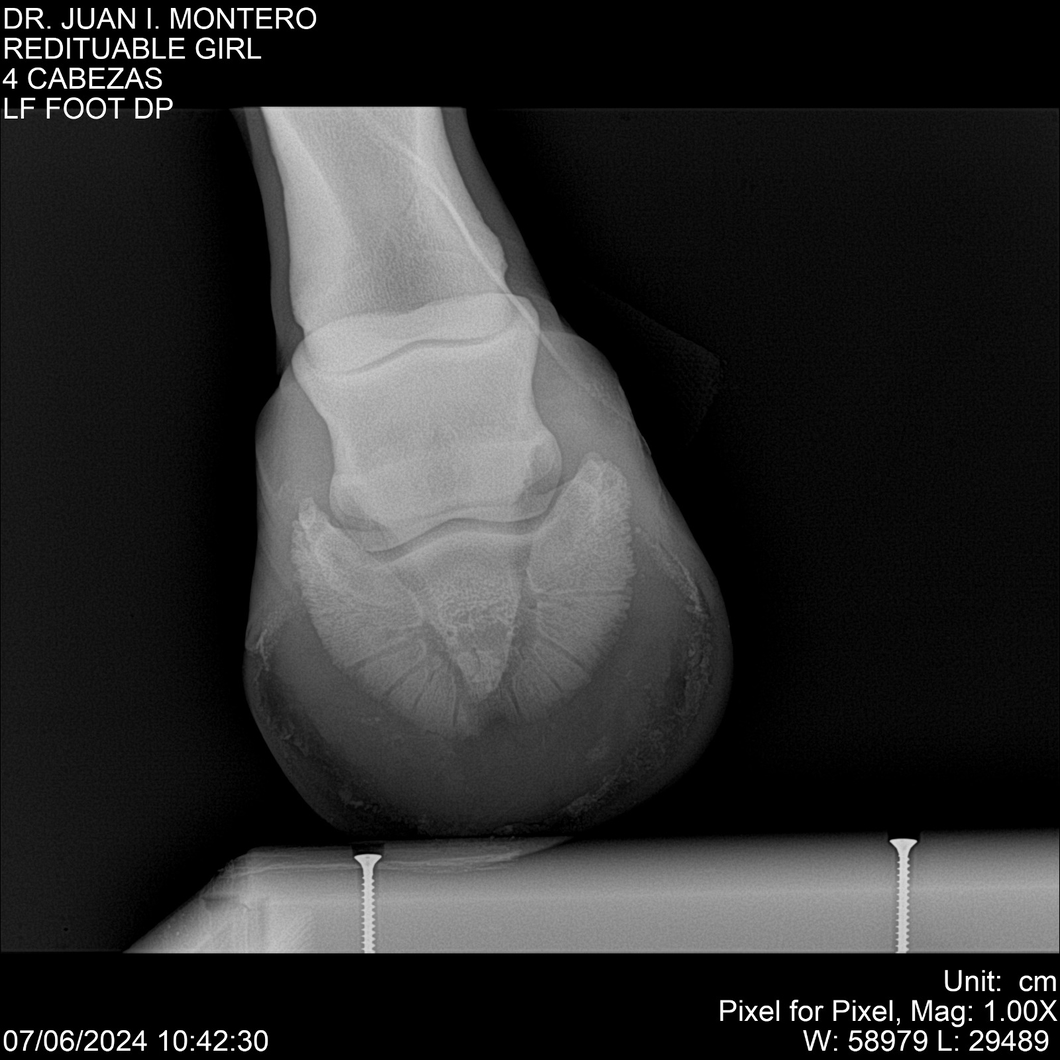

LOTE 19, REDITUABLE GIRL Lote Anterior Volver al remate Lote Siguiente Ficha Contacto Montevideo - Ficha del Lote Identificador: #281096 Categoría: Yeguarizos Montevideo - 79 Visualizaciones ClicData Contacto Empresa: Abelenda N. R., Walter Hugo Nombre*: Teléfono* : E-mail* : Mensaje Enviar Registrese gratis Este contenido Exclusivo está disponible sólo para usuarios registrados Ingresar